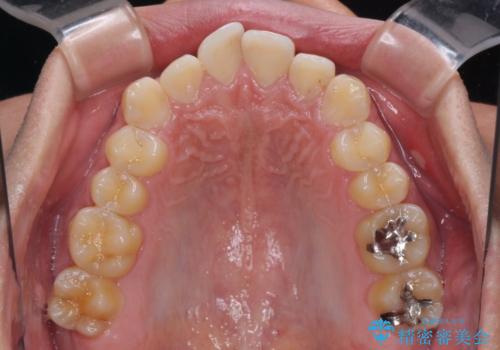

矯正治療後は、奥歯の銀歯をセラミッククラウンにて補綴治療を行うこととしました。

あっという間に歯列が整い、目立っていた銀歯もなくなり、清潔感のある口元になりました。